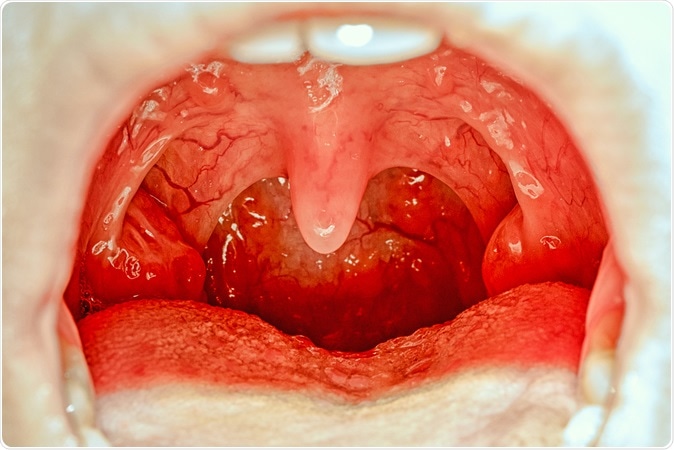

Open mouth showing tonsils. Image Credit: Elena11 / Shutterstock

The children who participated in the study were followed up until the age of 30 to determine their long term health risks. According to lead researcher Dr Sean Byars from the University of Melbourne, the tonsils and adenoids play an important role in the immune functions development of the child. There has been little research until now on the long term effects of removal of these organs in a person as a child. The tonsils and the adenoids prevent the entry of bacteria and viruses to the throat and lungs by fighting them off at the gates so to speak, explain researchers. They are usually removed when they are enlarged and they are obstructing the breathing. In children with enlarged tonsils and adenoids there is difficulty in breathing, recurrent chest and respiratory tract infections, tonsillitis, as well as recurrent middle ear infections.